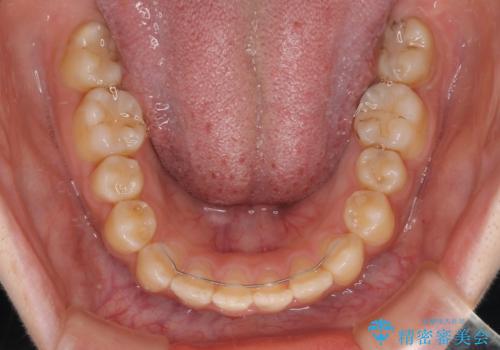

- 大学病院にて装置を装着したものの、治療が十分に受けることができないとのことで転院をされた患者様です。

上顎歯列が前方にあり、口元が閉じにくくなっていたため、既に装着されている装置を使用して上顎歯列全体を後方に移動させていくこととしました。

舌の突出癖があり、それが原因で上下前歯に隙間ができていたため、改善のためのトレーニングを行うように指示をしました。

舌の突出癖の影響か、なかなかスペースが閉じきらず、治療期間は予定よりも長期間となりました。

舌突出癖改善のトレーニングの重要性を認識することとなりました。